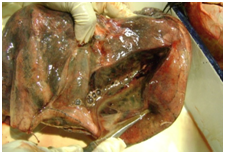

3. Multiple small creamy white spots over all the surfaces of all the lobes of both the lungs. On sectioning there was oozing of frothy pus mixed with blood (Figure 2).

Figure 2 Lungs on Sectioning.